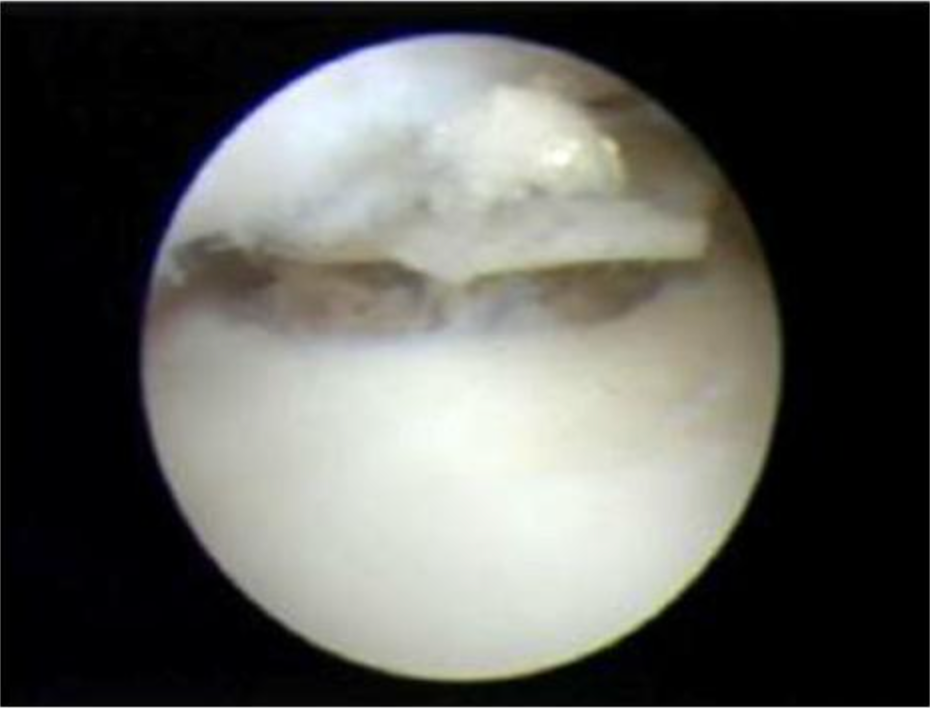

微骨折术通常与病变软骨清创联合进行,用刨刀去除缺损软骨层,必要时用锐匙修整至健康软骨边缘。去除软骨后暴露骨板,需判断骨板是否完整或存在额外骨缺损(骨软骨损伤),可用锐匙清理。钻孔器械包括专用工具或不同直径克氏针。纳米骨折术尖端直径 1mm,微骨折术尖端直径 2mm,器械尖端可弯曲 20-60° 以适应损伤部位,通过锤击形成微骨折,促使骨髓干细胞释放。研究表明,钻孔深度超过 9mm 可显著增加干细胞释放量。若损伤过大(2017 年标准已将临界值降至 1cm²),非负重腔隙不足以形成再生纤维软骨。